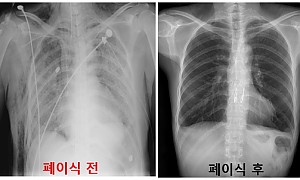

[기자회견안내] 가습기살균제 폐이식 피해자 실태보고서 및 피해사례발표

환경보건시민센터 보도자료 2016년 2월12일자 기자회견 안내 가습기살균제 사용 폐이식 피해자 14명, 판매 중단 4년이나 지난 2015년에만 폐이식 피해자 3명 확인 <사진: 가습기살균제 사용 가장 최근 폐이식한 피해자, 2016년 1월 21일 촬영> n 일시: 2016년 2월 15일 월요일 오후 2시 n 장소: 환경보건시민센터(대학로) n 주…